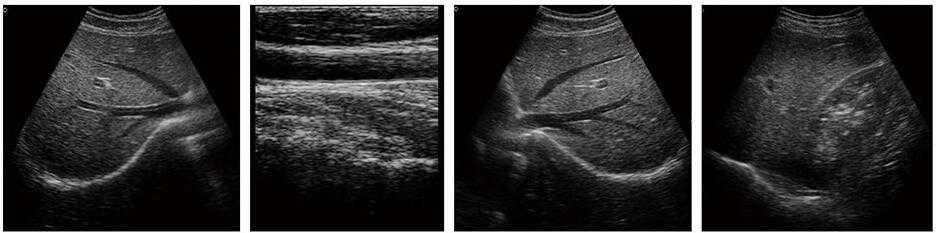

DW-370(技術版) 全數字超聲診斷儀-推車式黑白B超機

DW-370黑白B超機

全數字超聲診斷儀

3、適用于常規腹部、子宮附件、淺表組織等臨床檢查

5、用途說明:主要應用于腹部、泌尿科、婦產科、血管等